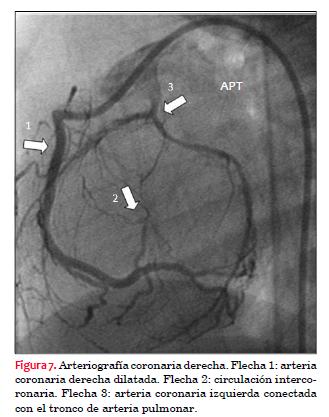

El diagnóstico se confirmó mediante aortografía y coronariografía selectiva de arteria coronaria derecha, realizadas bajo anestesia general, mediante angiógrafo Phillips Integris BH 3000, biplano, utilizando como contraste intravenoso iopromida 300 mg I/ml, utilizando 12 ml (figuras 6, 7 y 8).

Hasta hace poco tiempo la confirmación anatómica se realizaba mediante cateterismo cardíaco que permite observar: salto oximérico a nivel del tronco de la arteria pulmonar, dilatación e hipoquinesia del ventrículo izquierdo, insuficiencia mitral de grado variable, mostrar que desde la aorta solo emerge la arteria coronaria derecha, evaluar la circulación intercoronaria y a través de esta observar la arteria coronaria izquierda que se conecta con el tronco de la arteria pulmonar.